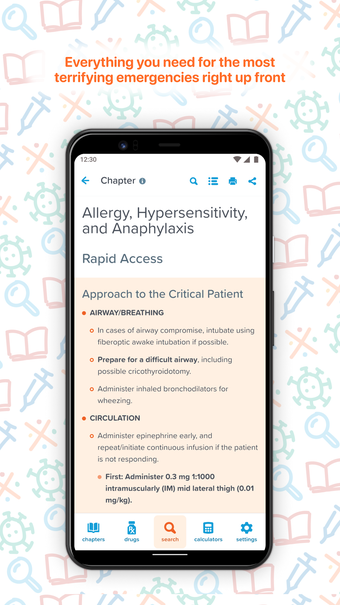

EM:RAP brengt alle beste en meest relevante informatie samen op één plek om het gemakkelijk te maken om klinische vragen te beantwoorden in een noodsituatie of een urgente situatie. Het is een echt uitgebreide, peer-reviewed, klinische bron voor spoedeisende en urgente zorggeneeskunde die u overal, altijd en op elk apparaat kunt gebruiken.